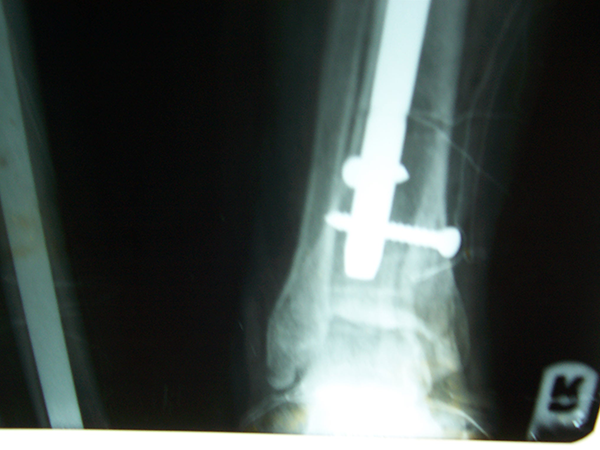

Case:19 Percutaneous fixation with Implants

A male patient, aged 78 years had been diagnosed to have a closed Pott’s fracture Left Ankle. He was treated operatively with Percutaneous fixation with Implants.

Pre-Operative

Post-Operative